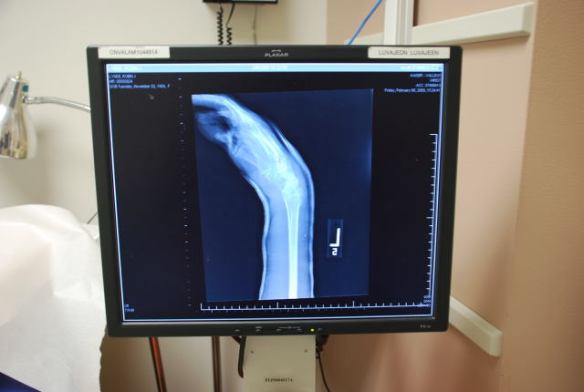

This is the surgeon's plan--where he is going to put the hardware. Pretend you are watching football and they are scribbling on the screen. It's just that the doctor doesn't have colored markers.